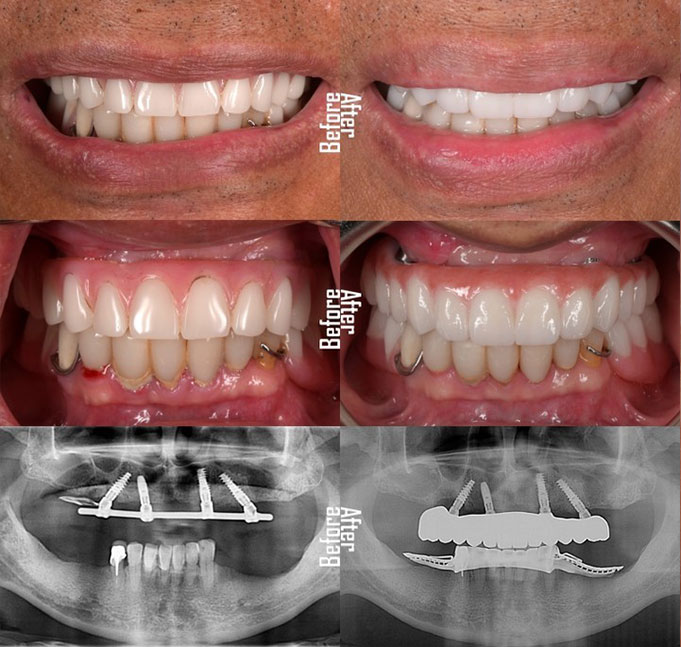

Before

After